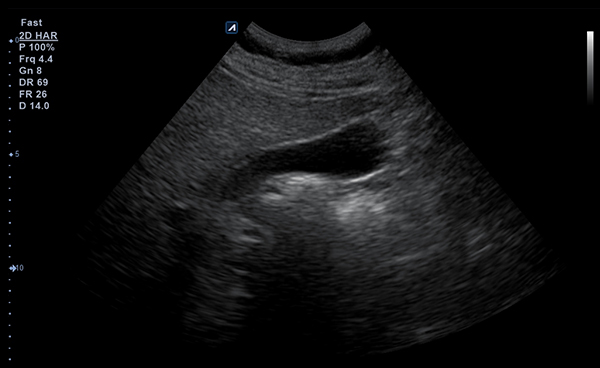

- Frequency1-6 MHz

- Dimension (height/width/depth)25.5 / 62.5/ 157mm

- Weight 175g

- Field of view 78°

- Max depth30 cm

- Imaging modesB-mode, CF, M, PW, PD

- DisplayMicrosoft Surface

- Battery300 min